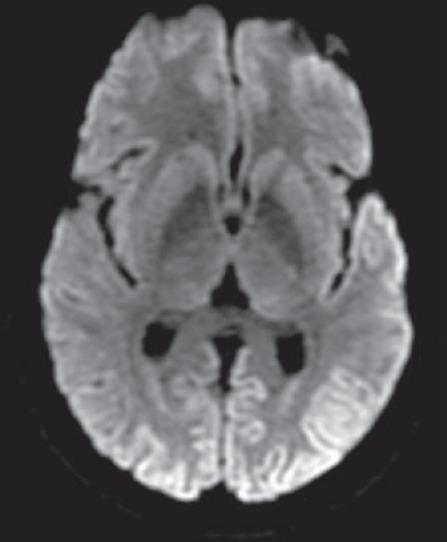

快速进展性认知衰退综合征——我们的经验

Syndromes of Rapidly Progressive Cognitive Decline-Our Experience.

RESULTS AND CONCLUSIONS

Out of 144 patients 42 had immune-mediated encephalopathy, 18 had Creutzfeldt-Jakob disease, 3 had Vitamin B12 deficiency, 63 had infection with neurocysticercosis, 7 had tuberculosis, 2 had HIV, 1 had herpes simplex encephalitis, 1 had neurosyphilis, 1 Whipples disease, 1 had Subacute Sclerosing Panencephalitis, 1 had Mass lesion, 3 had Frontotemporal dementia, and 3 had small vessel disease. Good majority of these patients have infective and immune-mediated causes and less number belong to degenerative group. Therefore, caution is needed to look for treatable cause as it carries a different treatment options and outcome.

结果与结论

144例患者中,42例患有免疫介导性脑病,18例患有克雅氏病,3例患有维生素B12缺乏症,63例患有神经囊尾蚴病感染,7例患有结核病,2例患有艾滋病,1例患有单纯疱疹性脑炎,1例患有神经梅毒,1例患有惠普尔病,1例患有亚急性硬化性全脑炎,1例患有占位性病变,3例患有额颞叶痴呆,3例患有小血管疾病。这些患者中绝大多数有感染性和免疫介导性病因,属于退行性病变组的较少。因此,需要谨慎寻找可治疗的病因,因为其治疗选择和结果不同。